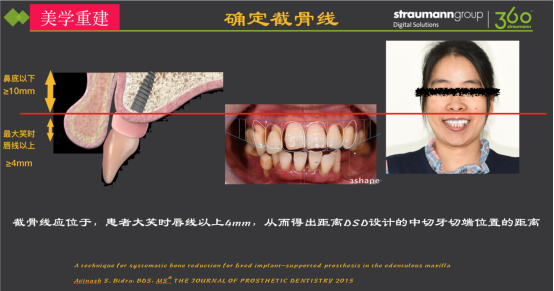

无牙颌固定修复存在美学风险

§ 义龈部分与软组织的边缘线在大笑时位于唇线以下为高分险(HER),应将其置于唇线以上以降低美学风险。患者为高笑线,因此需要截骨,截骨线应位于患者最大笑时唇线以上4mm。